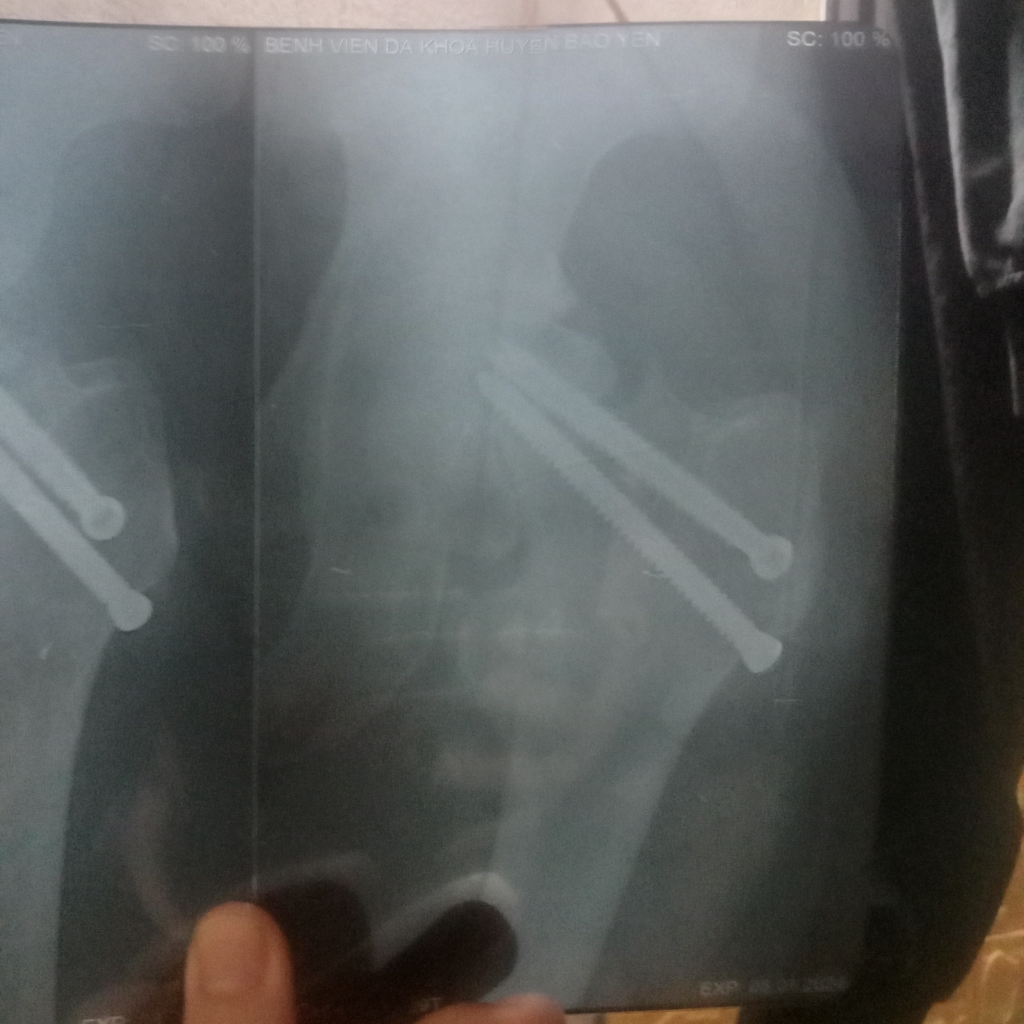

Đây là hình ảnh vít đinh của em ạ. Em thấy nó lệch lệch hay sao ạ bác sĩ.

Đinh này bs chẩn đoán hình ảnh sẽ giải thích em rõ hơn